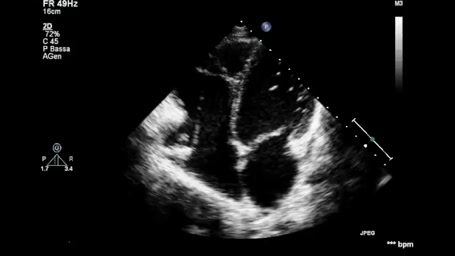

Cardiomiopatia ipocinetico dilatativa

Autore:

Andrea Barbieri